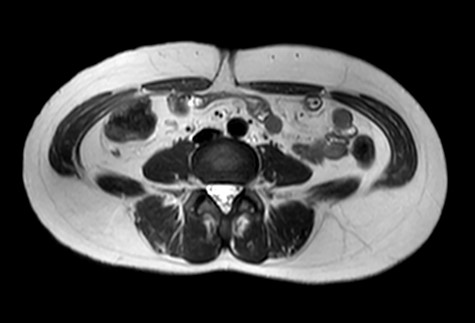

A 47-year-old woman was referred to us by her obstetrician. She developed a PHS after laparoscopic total hysterectomy with right oophorectomy performed 3 years previously. She reported pain with intermittent bulging on the superior aspect of the umbilical region. Clinical examination revealed a single hernia orifice at that location. Her height was 161.1 cm, with a weight of 60.1 kg, yielding a body mass index of 23.16 kg/m2. Her medical history included uterine fibroids and ovarian cysts. She had no history of smoking. Magnetic resonance imaging (MRI) revealed protrusion of adipose tissue at the upper side of the umbilical region, through a fascial defect measuring 9 × 13 mm; diastasis recti was also noted (Figs 1 and 2).

The patient did well after surgery. Follow-up MRI taken 10 days after surgery confirmed the absence of hernia and closure of the fascial defect (Figs 9 and 10).